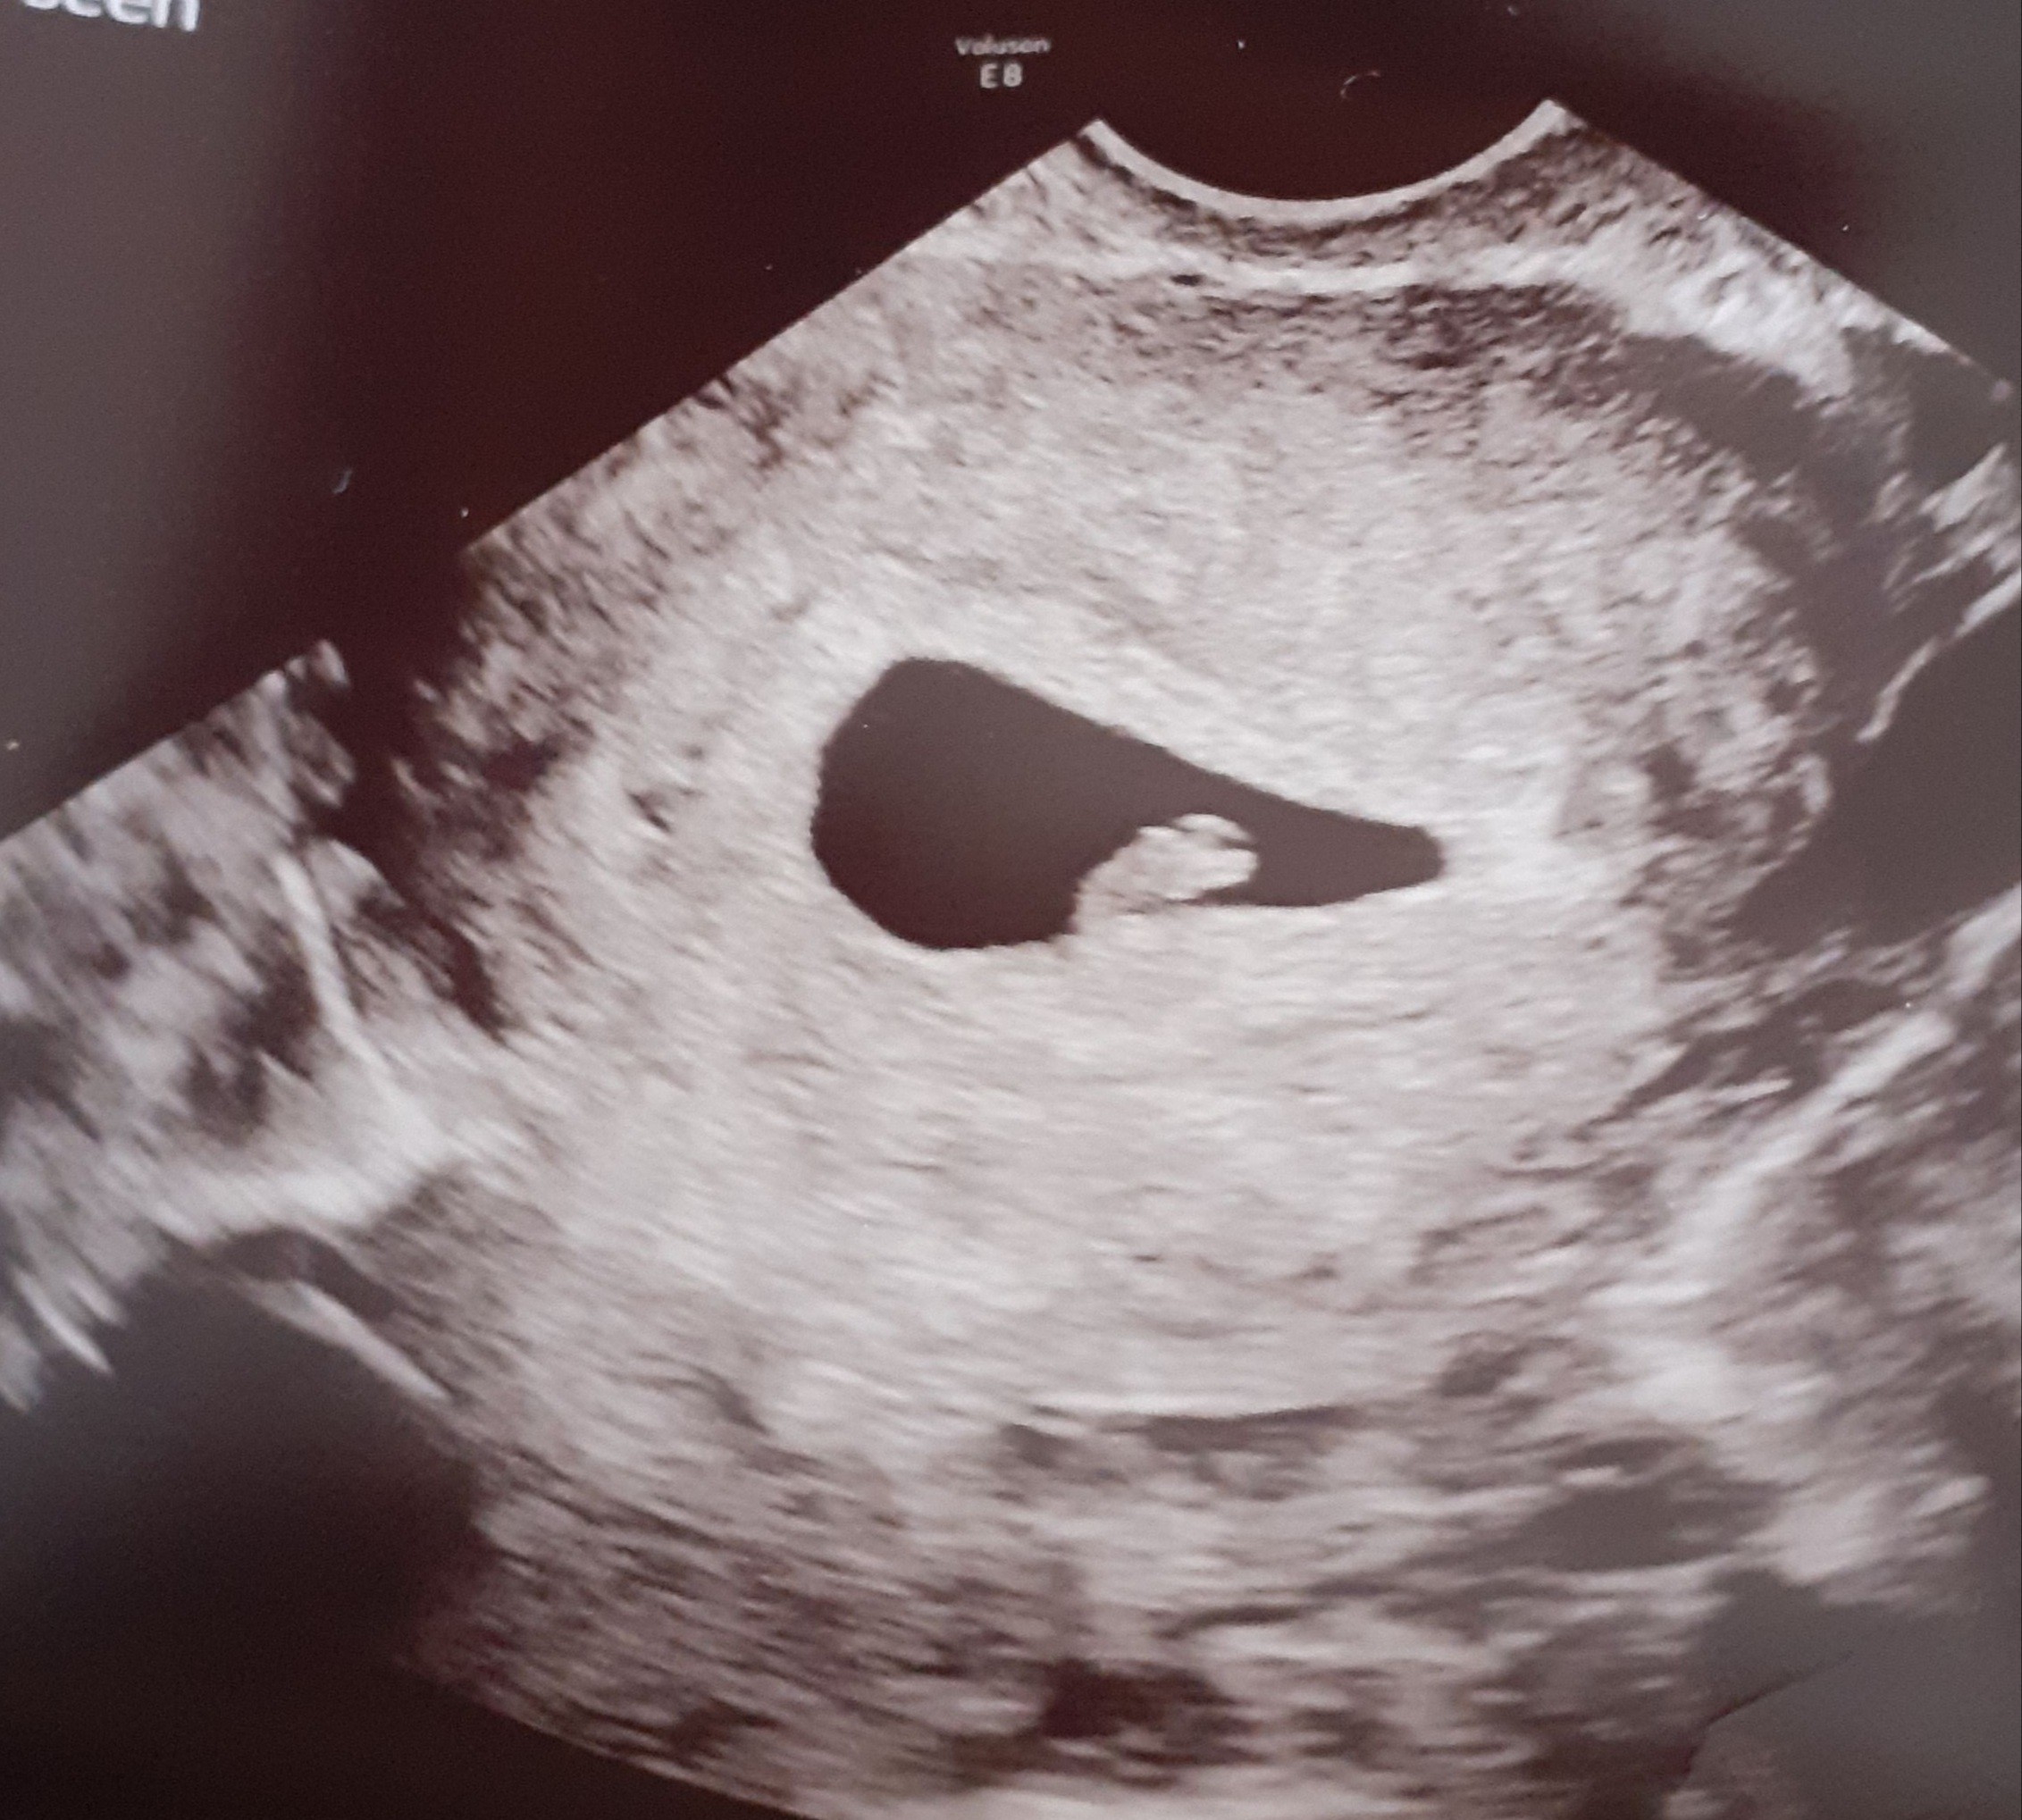

Kochana u mnie w 8tc zaniknęły dosłownie WSZYSTKIE objawy z dnia na dzień - zero mdłości, zero wrażliwości na zapachy, zero bólu piersi, spanikowana jechałam w sobotę na USG, a tam okruszek rośnie jak na drożdżach, serduszko bije jak dzwon - WSZYSTKO BEDZIE DOBRZE!